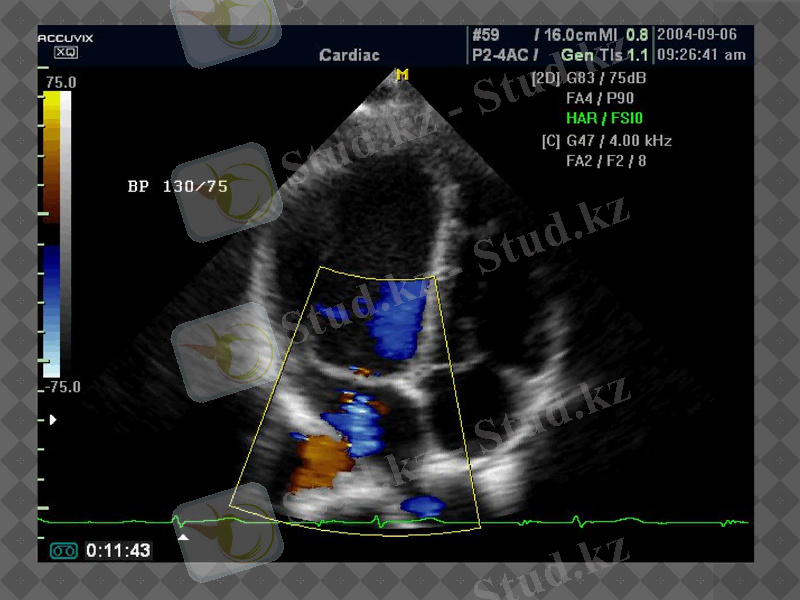

Эхокардиограмма

Регургитация

Кіші қан айналым шеңберінде гипертензия дамиды.